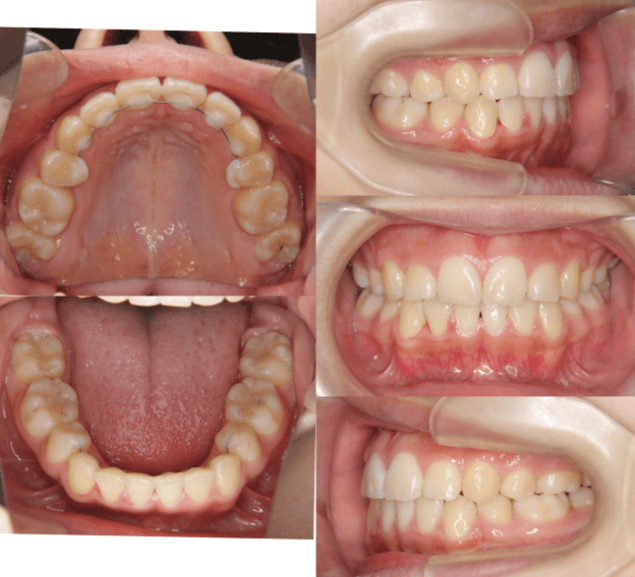

上歯前突+叢生症例 成長期

主訴 | 口元の突出感と歯並びが気になり、将来的な咬合状態を整える目的で来院された患者様です。 |

---|---|

診断結果 | 11歳1か月の女性。骨格的には日本人標準に近く、歯性の上顎前突および叢生が認められました。上下顎ともに歯列のスペース不足があり、永久歯の萌出や歯列の整列に支障をきたす可能性があると診断されました。 |

治療内容 |

|

治療後の経過 | 動的治療終了後は、上下顎の歯列が整い、口元の突出感と叢生が改善されました。審美的・機能的なバランスが取れた状態となり、現在は取り外し式リテーナーを使用し、保定期間に移行しています。 |

治療期間 | 動的治療期間:2年6か月 通院回数:25回 |

治療費用 | 720,000円 |